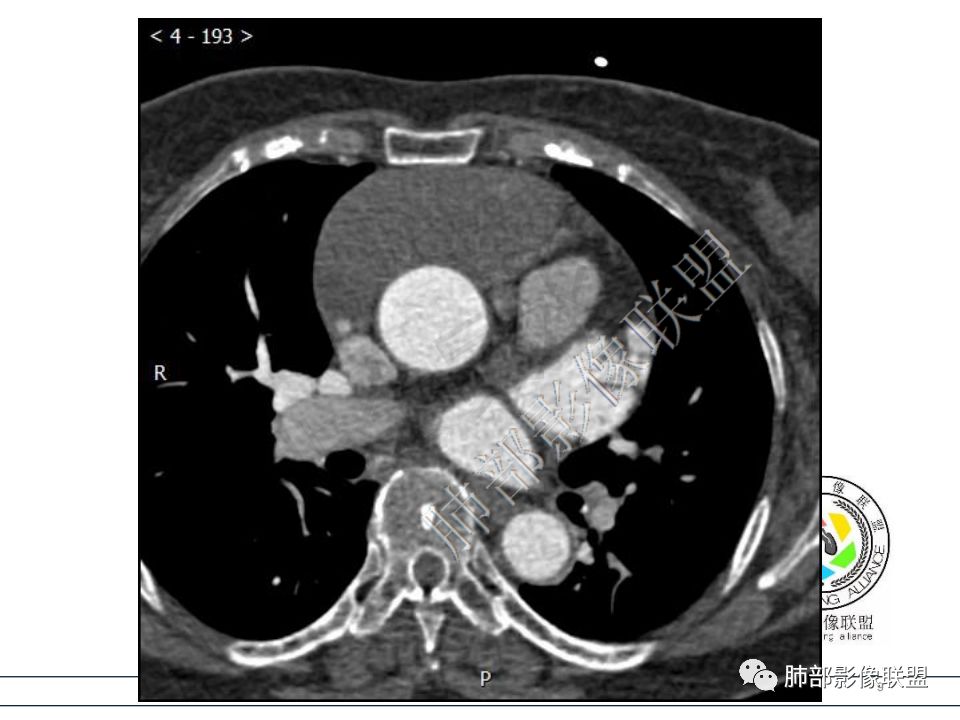

病例一考虑心包来源,病灶从大动脉根部一直延续到心底,明显不均匀强化,没有心包积液,良性?边缘强化,良性先考虑血管瘤。 医学百科网 | YxBaike.Com

病变位于心包,密度较低,边缘结节性强化,猜一个血管瘤。

定位心包,局部与右心房分界不清,右心房受压,冠脉受压,渐进性强化,没有心包积液,考虑心包来源或右心房游离壁来源血管瘤。 医学百科网 | YxBaike.Com

从心底沿右侧房室沟一直延伸至近膈面,心包来源可以解释的通;另外病变与右心室右心房之间的脂肪间隙一直存在。

心包海绵状血管瘤的CT特征为平扫呈边界清楚的圆形或者类圆形低密度肿块,对比增强扫描是诊断海绵状血管瘤的关键。动脉期肿瘤边缘可出现散在斑片状、结节状明显强化灶,接近同层强化大血管密度。静脉期散在的强化灶相互融合同时向肿瘤中央扩展。

渐进性强化,边界清晰,周围脂肪间隙存在,没有心包积液。

边界清晰,周围脂肪间隙存在,临近器官受压无受累。

心包海绵状血管瘤 医学百科网 | YxBaike.Com